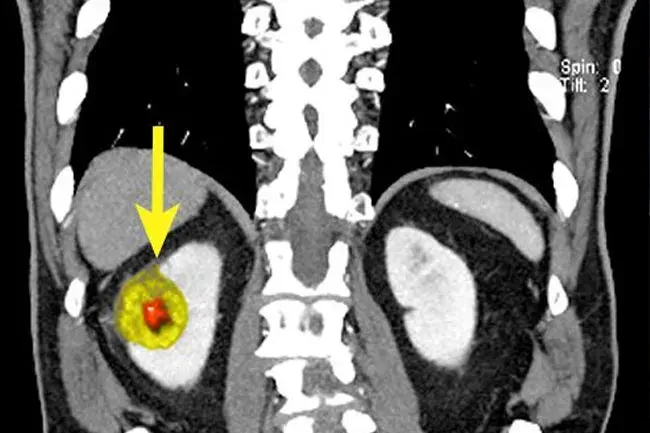

Diagnosi: test di imaging

Il medico può fare scansioni per dare un'occhiata più da vicino ai reni:

• Scansione di tomografia computerizzata (CT): i raggi X di diversi angoli vengono messi insieme per creare un quadro più completo.